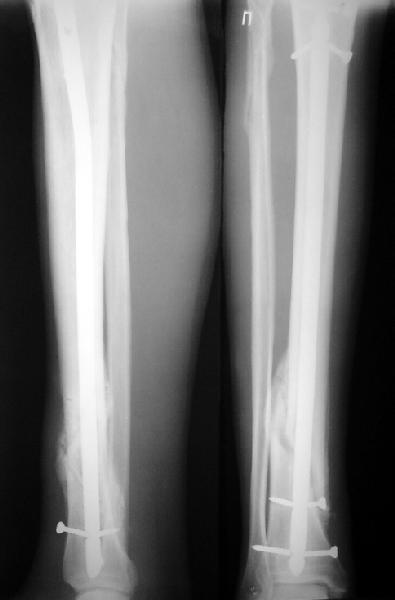

На мой взгляд, на снимках, приведённых Вами - неправильно сростающийся перелом дистальной трети большеберцовой кости, состояние после остеосинтеза интрамедуллярным гвоздём.

Как Вы пишите снимок под номером 1 - менсяц после операции, под номером 2- два месяца после операции.

Вы не послали послеоперационный снимок, поэтому трудно судить о состоянии редукции после операции.

Позвольте по поводу техники операции высказать своё мнение...

Установка с медиальной стороны гвоздя в области дистального фрагмента дополнительного шурупа помогло бы Вам репонировать и удержать перелом в анатомическом положении, предотвратило варусную деформацию и смещение по ширине.

Кстати, если можно пошлите послеоперационный снимок.

На мой взгляд внутрикостная фиксация переломов дистальной и проксимальной трети большеберцовой кости, за исключением поперечных, не очень хорошее решение вопроса, аппарат Илизарова или Тэйлора, позволяющие призвести закрытую анатомическую редукцию и отличное удержание отломков в период сращения.

Пример, приведённый Вами в нашей дискуссии по времени нагрузки после остеосинтеза не совсем удачный... Ваш больной имеет счастье, что первым согнулся проксимальный замыкающий винт, а не дистальный и гвоздь не пенетрировал голеностопный сустав.

Ok. А также и следующий, в 3 месяца.